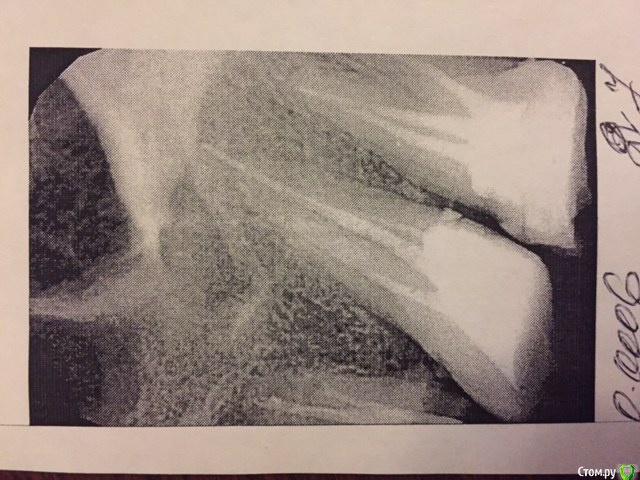

Подскажите пожалуйста. Лечила зуб (депульпировали). После этого- болит вся левая сторона лица, заложено ухо, нос и болит даже левый глаз:(

Может ли это быть от пломбы?

от  пломбы нет.

После лечения каналов боли бывают, но не такие как Вы описываете

Больше похоже на гайморит.